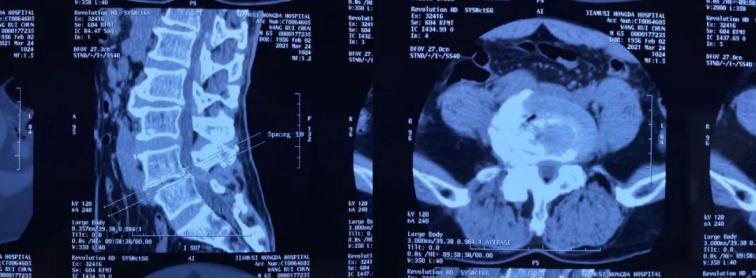

術(shù)前CT

術(shù)前MRI